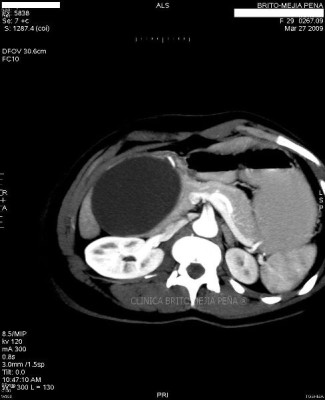

Metástasis hígado fase venosa